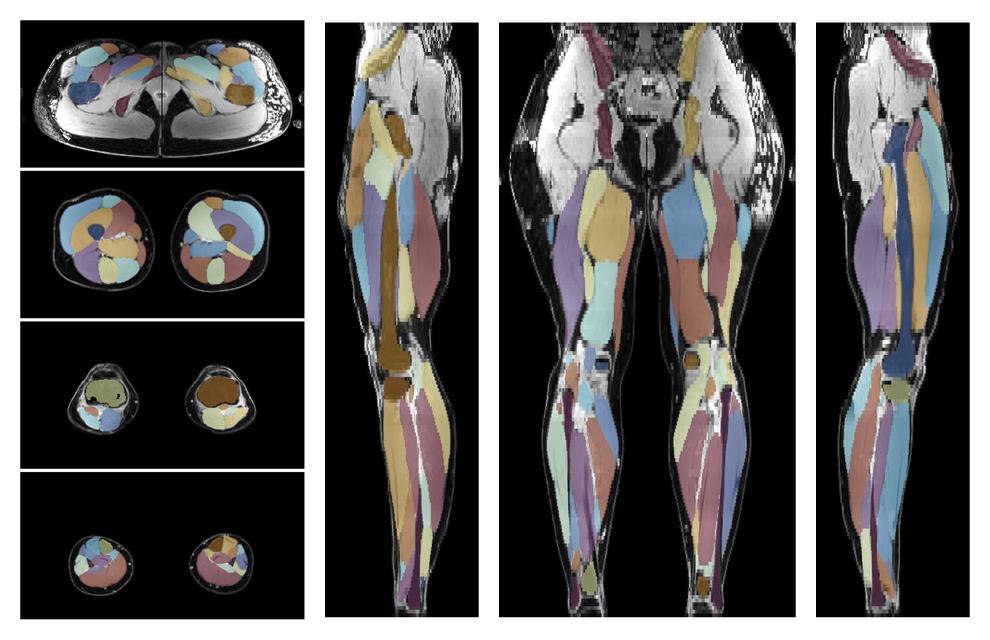

• Automated muscle and bone segmentation.

Overlay of automated muscle segmentation labels on dixon water image.